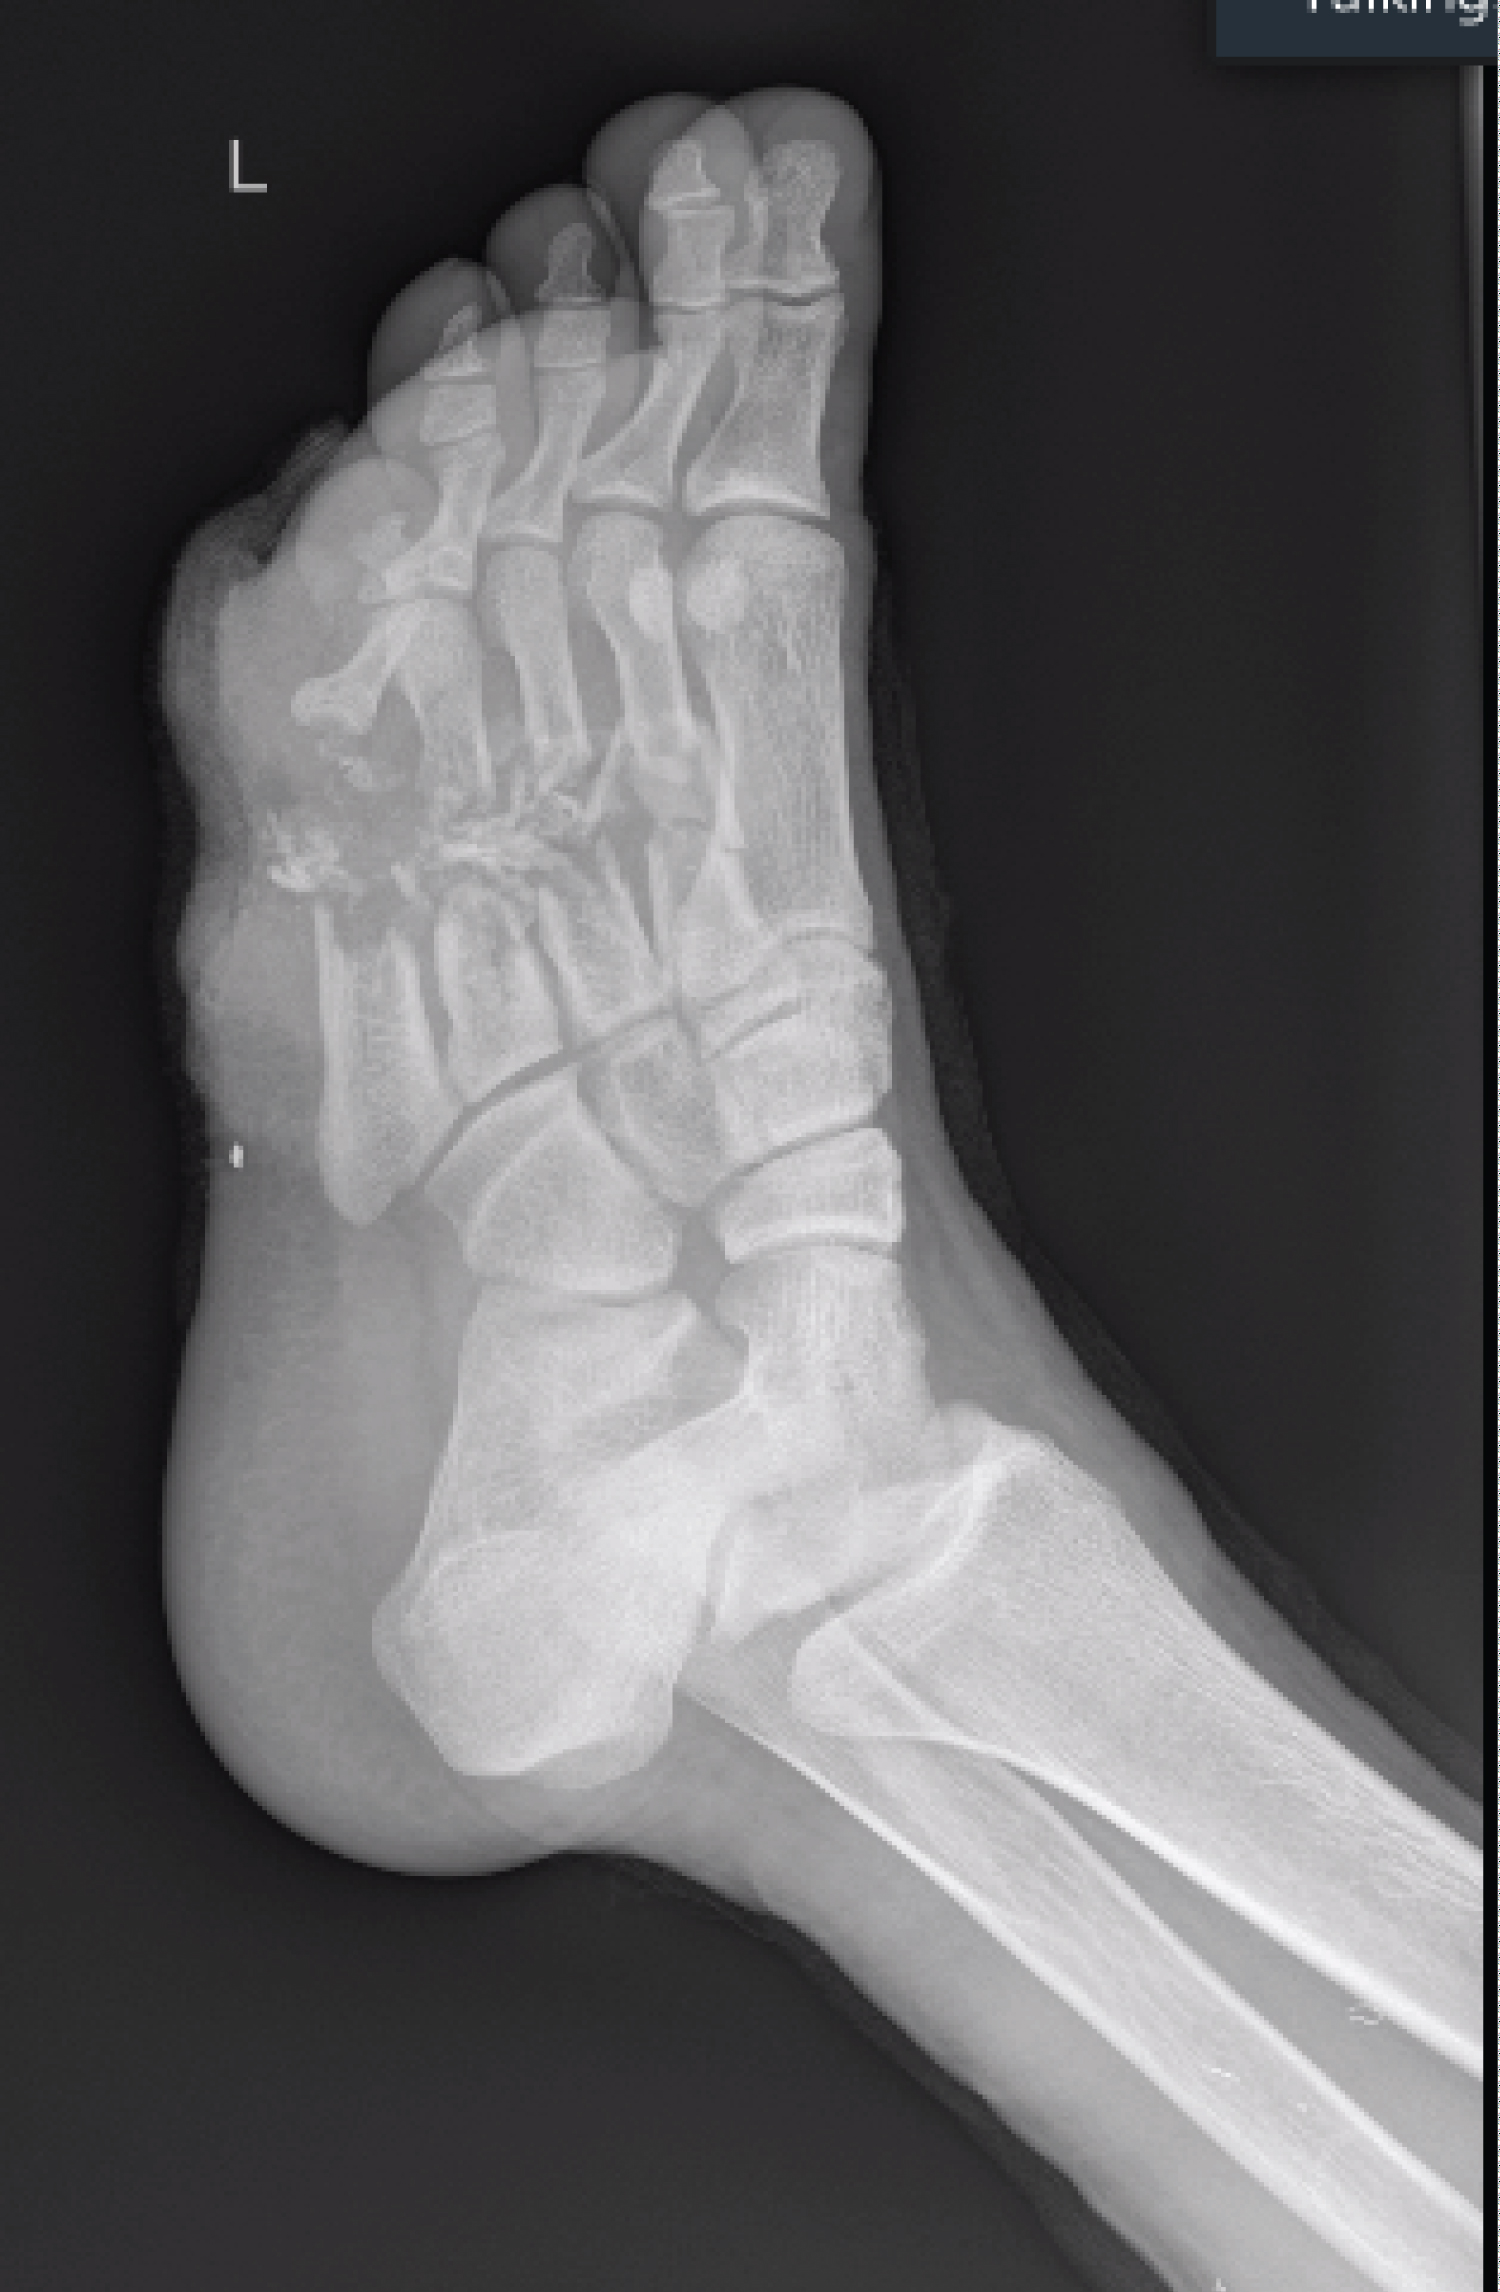

A 25-year-old soldier was involved in a blast and suffered multiple superficial and deep soft tissue injuries. His main osseous injuries were in his left foot, where he suffered fractures of his second, third, fourth and fifth metatarsals. These metatarsal injuries were open fractures with segmental bone loss and soft tissue loss with significant contamination (Figure 1 and Figure 2). He also had a large soft tissue defect from damage to his calf complex with no involvement of the neurovascular structures on the unilateral side (Figure 3). He was initially managed as per ATLS principles ensuring physiological stability. He then went on to have acute debridement of the multiple soft tissue injuries planned in conjunction with the plastic surgery team.

Figure 2: Radiograph shows segmental bone loss. View Figure 2